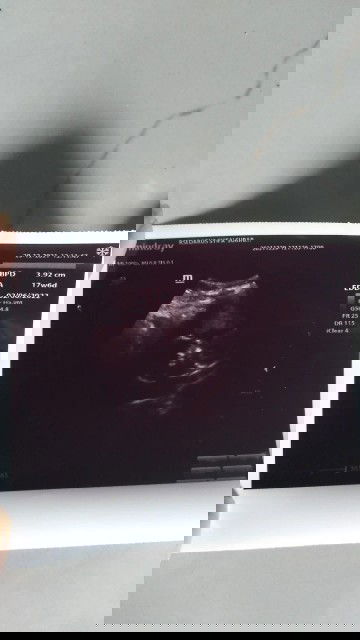

Usia sesuai dengan usia kehamilan atau tidak?

Usia kehamilan saya sudah masuk 22 minggu tpi perut belum kelihatan besar . Dan ini foto usg waktu usia 17 minggu . Apakah sesuai dngn usia kehamilan saya dok?